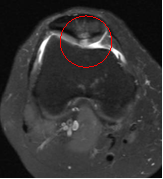

Chondromalacia patellae

Normal